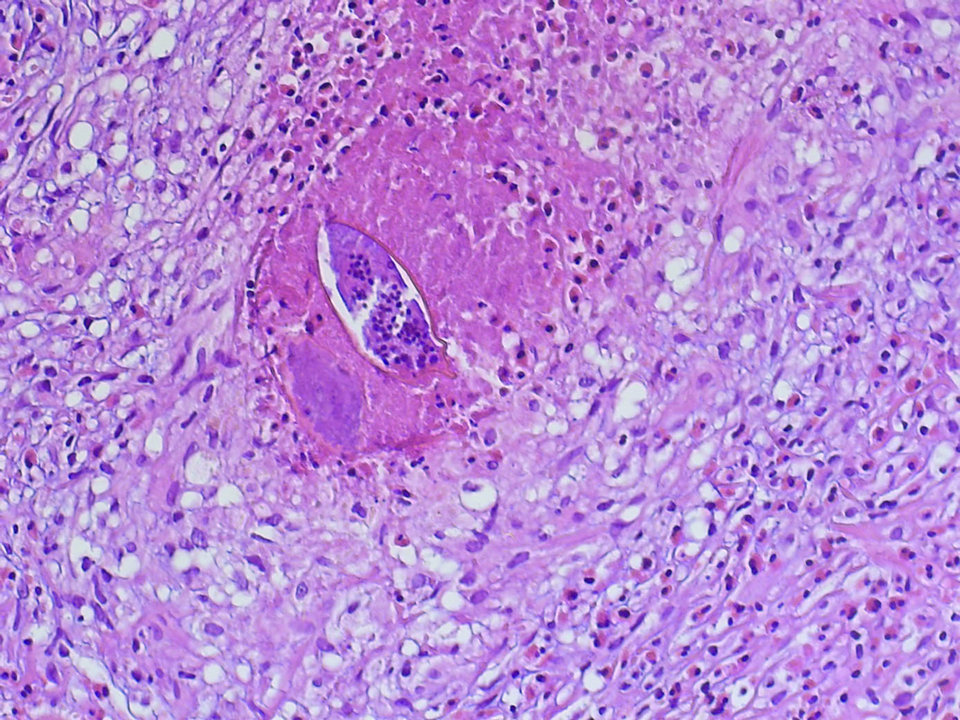

Nachträglich wurde der Wurmfortsatz biopsiert. Neben einer eosinophilen Entzündung fanden sich auch Schistosomeneier. Nachträglich wurde der Wurmfortsatz biopsiert. Neben einer eosinophilen Entzündung fanden sich auch Schistosomeneier. © Mit freundlicher Genehmigung von Dr. Christian Kraef, c.kraef@uke.de, Department of Tropical Medicine, Bernhard Nocht Institute for Tropical Medicine & I. Department of Medicine, University Medical Center Hamburg-Eppendorf, Hamburg

Dr. Christian Kraef von der I. Medizinischen Klinik am UKE und seine Kollegen können im Blut und Ejakulat über PCR den Befall mit Schistosoma haematobium nachweisen. Zusätzlich finden sie vitale Eier des Pärchenegels in der Spermaprobe. Die nachträgliche Histologie des entfernten Appendix identifiziert ebenfalls Granulome mit Wurmeiern. Eine dreitägige Therapie mit Praziquantel (40 mg/kg KG oral) führt zur vollständigen Ge­nesung.

Neben einer eosinophilen Entzündung fanden sich auch Schistosomeneier. Neben einer eosinophilen Entzündung fanden sich auch Schistosomeneier. © Mit freundlicher Genehmigung von Dr. Christian Kraef, c.kraef@uke.de, Department of Tropical Medicine, Bernhard Nocht Institute for Tropical Medicine & I. Department of Medicine, University Medical Center Hamburg-Eppendorf, Hamburg